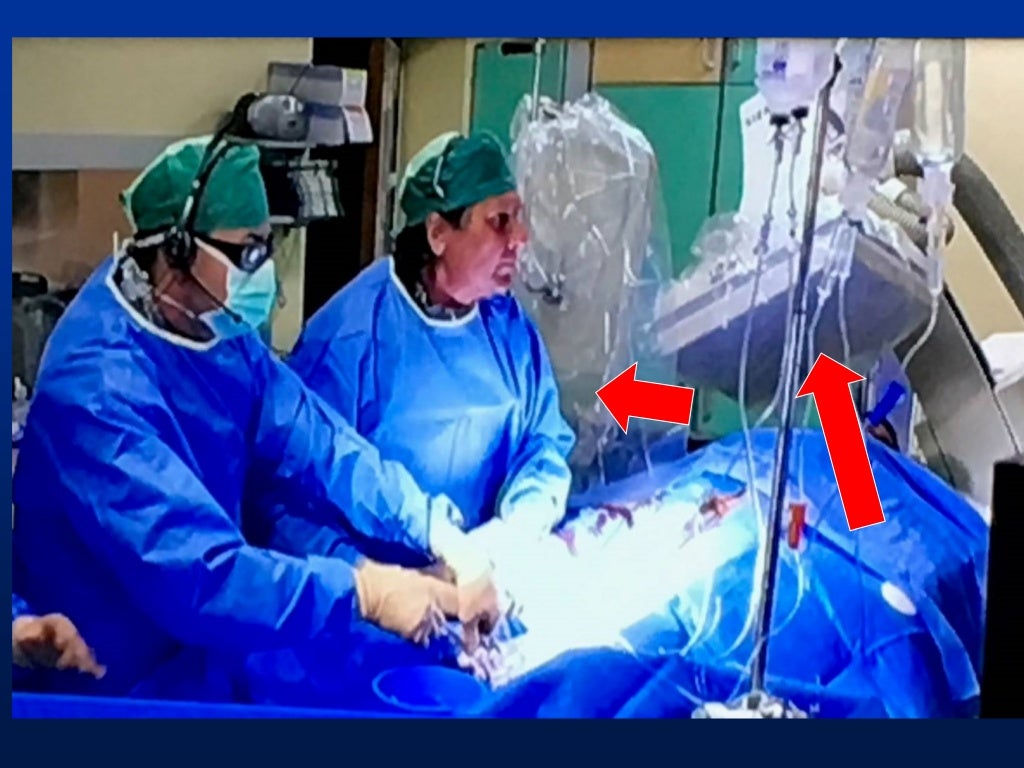

I) use collimator to set minimal useful field size, keep image intensifier in close proximity.

This principle confers to physicians the responsibility for reducing as much as possible the dose of radiation during cardiovascular procedures to minimize the. Radiation exposure can be accumulated over the time of. We strive to perform only tests that are necessary and to use just enough radiation doses to provide a high quality image to help your.

There are various types of shielding used in the reduction of radiation exposure including lead aprons, mobile lead shields, lead glasses, and lead barriers. The purpose of this article is to (a) describe the importance of educating radiology personnel, patients, and referring clinicians about the concerns over ct radiation, (b). Every diagnostic medical procedure involving ionizing radiation needs to minimize radiation exposure without compromising the benefit for the patient.